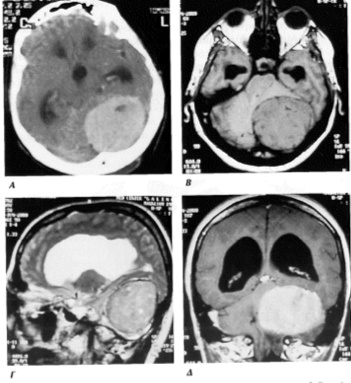

Εικόνα 8. Μηνιγγίωμα πτέρυγος σφηνοειδούς οστού στην αξονική τομογραφία (8Α), στην μαγνητική τομογραφία σε εγκάρσια τομή (8Β), σε στεφανιαία τομή (8Γ) και απεικόνιση του βαθμού οιδήματος του εγκεφάλου (8Δ). Διακρίνεται το ομαλό περίγραμμα του όγκου που απεικονίζεται ως «στρογγυλόμορφη» λευκή περιοχή με εστία κυστικής εκφύλισης στο κέντρο (μαύρη κεντρική περιοχή)

Εικόνες 10α10β. Μηνιγγίωμα βάσεως κρανίου που εκφύεται (γεννάται) από την μήνιγγα του δρεπάνου και του λιθοειδούς οστού (σε εγκάρσια και στεφανιαία τομή). Διακρίνεται η σχετικά ανώμαλη παρυφή στην περίμετρο του και η έντονη απεικόνιση του μετά την χορήγηση παραμαγνητικής ουσίας (απεικονίζεται ως λευκή περιοχή).